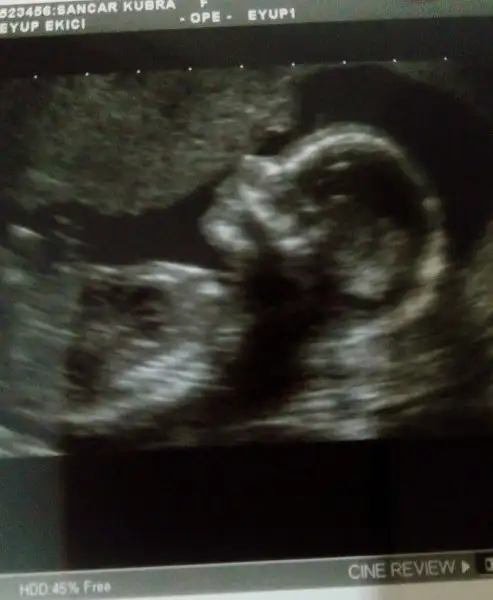

Selam kızlar uzun zamandır giremiyorum ikili testim de down sendromu riski yüksek çıkmıştı hatırlayan vardır belki bugün ayrıntılı bakıldı yavrum çok sağlıklı çok şükür oğluma bir kız kardeş geliyor Allahım herkesin evladına sağlık versin kimseyi evladıyla sınamasın

• IMG_20180206_140444_988.webp

Sonucunun iyi çıkmasına cok sevindim cnm gözün aydın hayırlı olsun..kesin kız deilmi yani

doktor sadece senin kızın olacak dedi. Pek söylemek istemedikleri için kesin mi diye soramadım. sırada benden önce olan kadın çocuğun cinsiyetini henüz öğrenemedim bakabilirmisiniz dedi doktor birşey demeden sekreterleri atladı doktora öyle şeyler sormayın diye bende detaylı ultrasondan önceki normal ultrason odasındaki doktora sormuştum denk gelirse söylüyorum denk gelmezse söylemem demişti. detaylı ultrason odasındaki sekreterler soru sormayın diye çıkışınca doktor incelik gösterip diğer kadınada banada kızımızın olacağını söyledi.